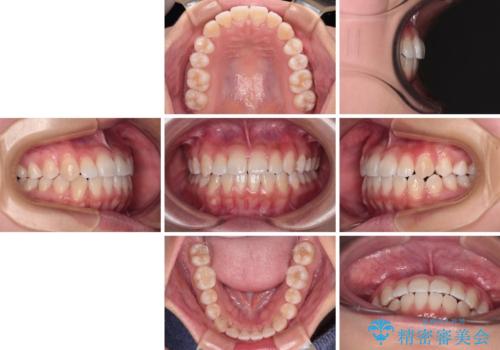

- メタルブラケット

- 1年2ヶ月

- 10-30回